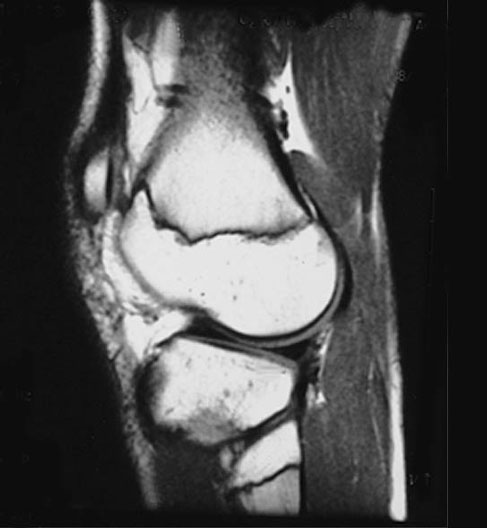

Knee MRI - Sagittal View

1. Bone marrow of femur

2. Condylar surface of femur bone

3. Articular cartilage

4. Lateral meniscus

5. Head of fibula